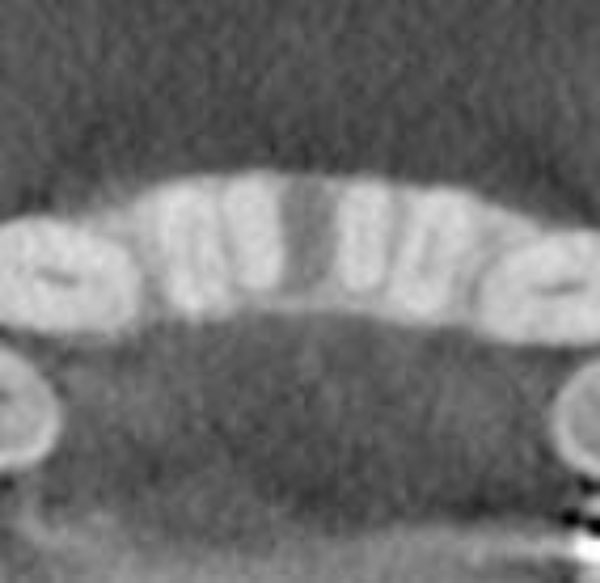

Clinical examination revealed the space formation between teeth 24 and 25 (Fig. 1a). The overlying mucosa and gingiva appeared normal in color. Deep probing elicited bleeding from the problem site. Radiographic evaluation revealed a well-circumscribed, low-density, radiolucent lesion between the mandibular central incisors, with spacing between teeth 24 and 25 (Fig. 1b) as well as thinning and expansion of the buccal and lingual cortical plates (Figs. 1c-1e). No other pathology was detected by the oral and maxillofacial radiologist on the images.

Fig. (1d).

Three-dimensional image showing the loss of vertical dimension and buccolingual expansion of the alveolar bone.

A well-circumscribed, low-density, radiolucent lesion presented between the two mandibular central incisors. The buccal and lingual cortical plates appeared to be thinned and expanded (Fig. 1f).